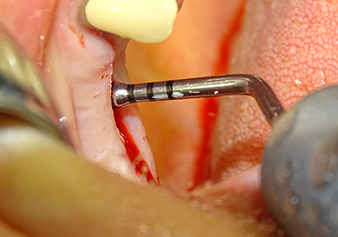

Following an intermediate check (Fig. 4) a further preparation step was performed (Fig. 5). Afterwards, the hydraulic Z35P instrument was used to lift the membrane to the desired position (Fig. 6 and 7). This was followed by further piezosurgical preparation of the implant bed, concluded with a rotary bur and shoulder milling cutter up to the implant diameter of 4.8 mm. Before the implant was inserted, the augmentation material (particle size approx. 0.8-1.6 mm) was introduced underneath the Schneiderian membrane (Fig. 8).

The implant bed is widened to 3.0 mm with the I3A instrument

Fig.5: In the next step, the implant bed is widened to 3.0 mm with the I3A instrument (power 100%, coolant 80%). The depth marks reliably prevent the preparation from going too deep.